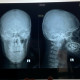

Alo dok izin tanya, pasien post KLL motor

Saat dilakukan pemeriksaan pasien sulit membuka mulut hanya dpt 2jari lalu pipi kanan terlihat terdapat benjolan berbeda dari pipi kiri.

Setelah di rontgen hasilnya seperti ini dok

Kira2 apakah ada fracture ya dok